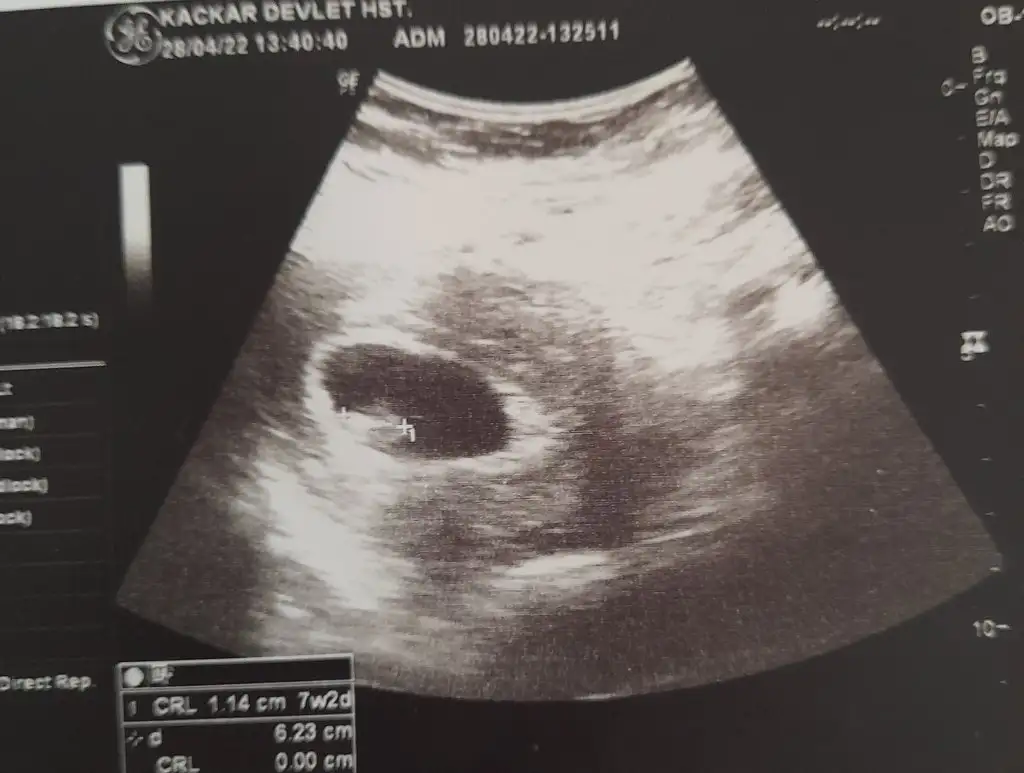

Buda ilk az once gonderdigim bugunkiydi 12 haftalik. Simdi attigim 7 haftalikValla hicbisey gormuyorum kese nerde gııı

Buda ilk az once gonderdigim bugunkiydi 12 haftalik. Simdi attigim 7 haftalik